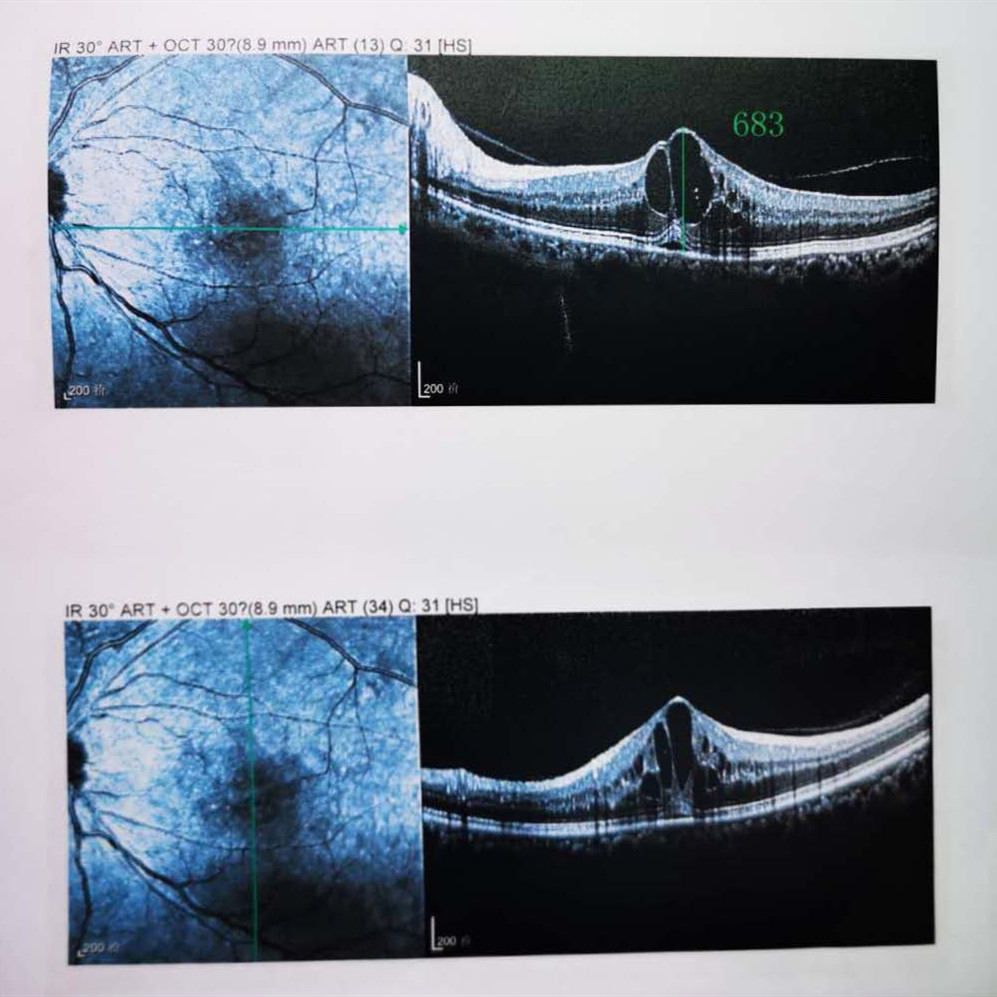

檢查結果顯示,武先生并沒有近視,右眼視力為1.0,但是左眼視力只有0.4,而且左眼視網膜各分支靜脈迂曲擴張,全網膜面見火焰狀出血,黃斑區(qū)高度水腫、滲出,黃斑中心凹厚度約683um。

(武先生初次就診眼底OCT檢查圖)

而正常的矯正視力是1.0,黃斑中心凹厚度在200um左右。

“你這黃斑都腫到正常人的三四倍大了!”廈門眼科中心吳國基院長醫(yī)生告訴武先生,“你這是左眼視網膜中央靜脈阻塞伴黃斑水腫,你左眼的視力下降、看東西變形,是因為你左眼視網膜的中央靜脈發(fā)生了阻塞、出血,導致眼底黃斑水腫了。”

那么,武先生的視力恢復情況如何呢?幸運的是,經過兩次玻璃體腔注藥術,武先生左眼的黃斑水腫得到明顯改善,視力已經恢復到0.8。

(武先生出院時眼底OCT檢查圖)